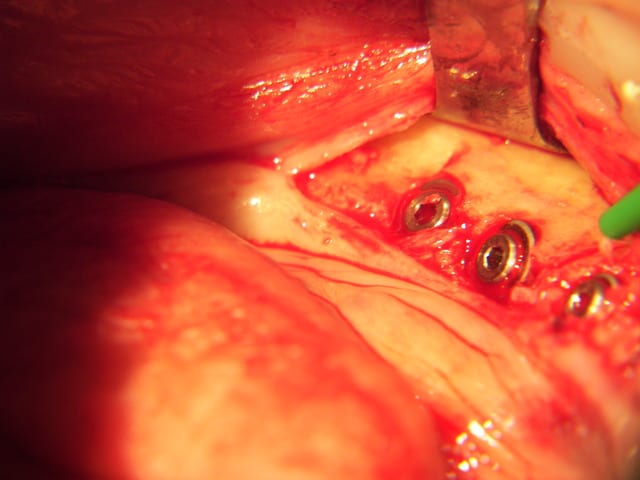

ce que je considère comme pas simple du tout expansion symphise.

ce fut long (pas loin de trois heures) mais bon!

la suite

combiné de mini expansion et classique implants courts 8 et 6 mm 4 et 4,6 de diam.

fente verticale, decharges latérales expanseurs, forets pour finir, implants lisse et pose de 3 Axioms